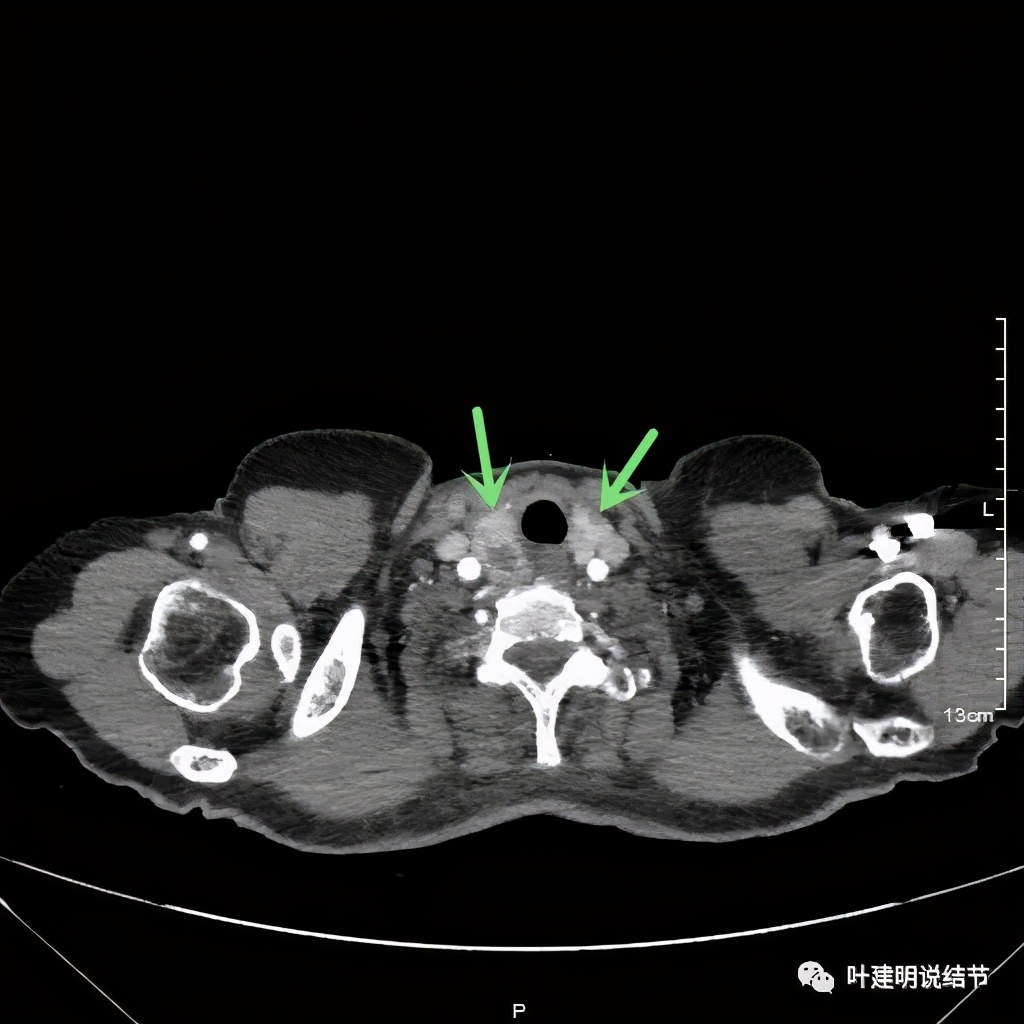

上图红色示肿瘤,黄色示气管,蓝色示上腔静脉

上图红色示肿瘤,黄色示气管,蓝色示上腔静脉,肿瘤已经快要消失了的层面,它距离隆突只有2点几厘米了,位置很低

我们由胸顶再往颈部一层一层看,结果真的肿瘤是与右侧甲状腺相连的!那么应该可能是甲状腺来源的纵隔肿瘤(胸内甲状腺肿瘤)。这样的话,其他的边缘界限清楚,这种密度以结节性甲状腺肿可能性大,不太像甲状腺恶性肿瘤。那么与气管间估计也是紧密靠着而已,不会是侵犯的。所以我们商量后就不穿刺,打算直接手术切除。术前做了冠脉CT,也有点问题,好在冠脉狭窄程度不重: